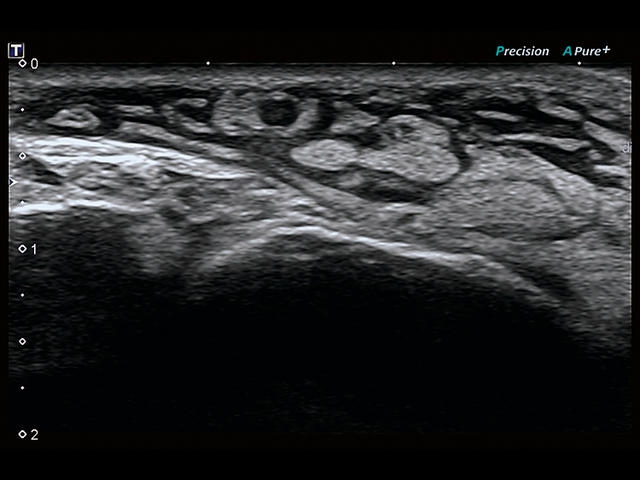

Обновленная версия легендарного УЗ-сканера. Стационарный аппарат экспертного класса Aplio 500 Toshiba NEW, визуализирует анатомические структуры в высоком разрешении. Модель позволяет выявить микрокальцификаты, новообразования, нарушения в работе сердца, сосудов и мышц. Присутствует функция виртуальной эндоскопии, 4D-сканирования, эластометрии тканей, УЗИ с контрастированием. За повышение качества изображения отвечают технологии ApliPure и Superb Microvascular Imaging. Первая задействует возможности пространственного и частотного кодирования, формирует цельный визуальный ряд с сохранением клинических маркеров. Вторая улучшает отображение микрососудистого русла, используя доплеровский эффект. Модель оснащена 21-дюймовым монитором, имеет 4 активных порта. Возможно подключение педиатрических, интраоперационных, лапароскопических и чреспищеводных датчиков.

• MicroPure. Высокотехнологичное решение в области выявления микрокальцификатов – маркеров новообразований злокачественного типа. Маркеры идентифицируются путем изучения затененных изображений целевого участка. Микрокальцификаты отображаются в виде белых пятен.

• SMI. Опция, упрощающая визуализацию микроциркуляторного русла. С ее помощью обследуются сосуды с низкой интенсивностью кровотока, изучаются наиболее тонкие структуры. SMI упрощает диагностику новообразований, минимизирует вероятность ошибки.